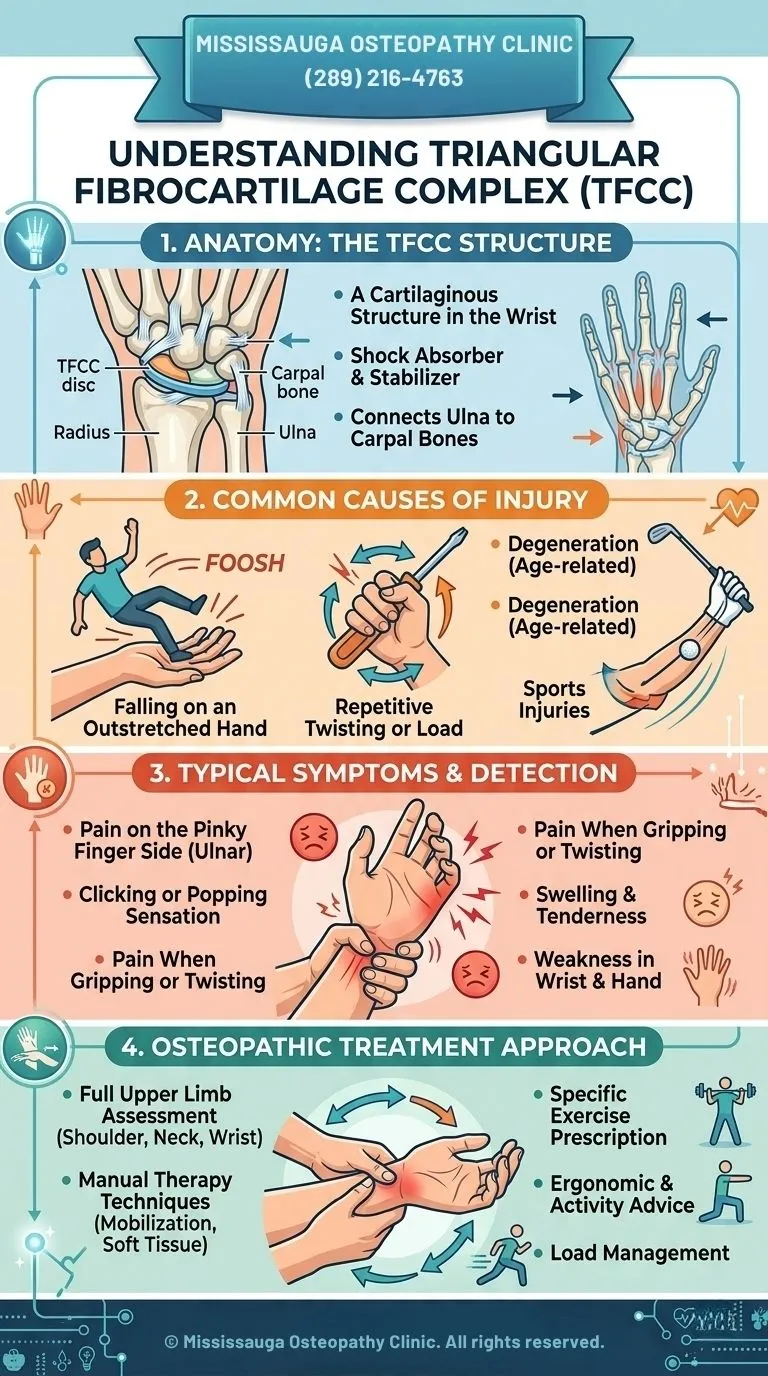

Triangular fibrocartilage complex (TFCC) injuries affect the ulnar side of the wrist—the side closest to the little finger. Mild cases may feel like a simple wrist sprain, but due to the complexity of the wrist’s soft tissues, these injuries can significantly impact stability and function.

The TFCC plays a crucial role in supporting and stabilizing the wrist joint, allowing smooth and controlled movement. When this structure is damaged through trauma or gradual degeneration, it can lead to persistent pain, weakness, and limited mobility.

This guide explains the structures involved, how these injuries occur, how they are diagnosed, and the treatment options available.